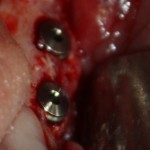

Через три месяца результат:

можно ставить формирователи и заканчивать лечение:

В указанном выше случае использование костных блоков просто невозможно.